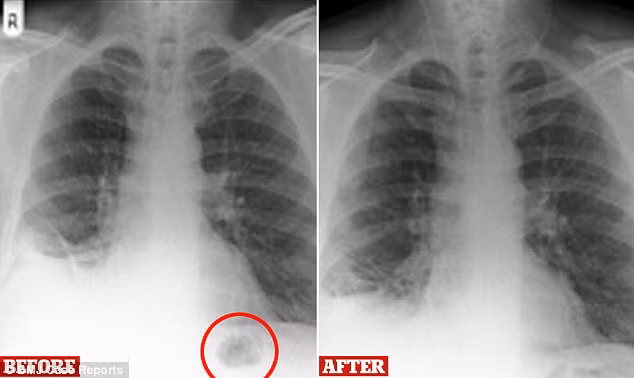

Với tình trạng như vậy, người đàn ông đến từ Preston, Anh được tiến hành phẫu thuật khẩn cấp. Đến lúc này các bác sĩ mới phát hiện khối u trong phổi hóa ra chỉ là một chiếc nón đồ chơi. Đây là thứ mà bệnh nhân vô tình hít qua đường khí quản, trú ngụ trong phổi từ 40 năm về trước. Chính dị vật này là nguyên nhân khiến phổi của người đàn ông bị tổn thương.

Bệnh nhân cho biết đây là chiếc nón trong bộ ghép hình mình được tặng vào sinh nhật 7 tuổi. Cùng với quá trình trưởng thành, đường hô hấp của anh đã thích nghi được với dị vật nên món đồ chơi mới lâu bị phát hiện đến vậy. Chỉ 4 tháng sau khi loạt bỏ chiếc nón giao thông ra khỏi cơ thể, các triệu chứng nguy hiểm của bệnh nhân 47 tuổi cũng giảm hoàn toàn.